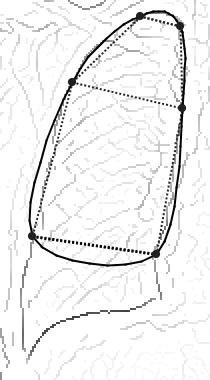

| SketchSnakes: Sketch-Line Initialized Snakes for Efficient Interactive Medical Image Segmentation, T. McInerney, Computerized Medical Imaging and Graphics, 32, 2008, pages 331-352. |

Topology Adaptive Snakes, T. McInerney, D. Terzopoulos, Medical Image Analysis, 4(2), June, 2000, pp 73-91. |

Sketch Initialized Snakes for Rapid, Accurate, and Repeatable Interactive Medical Image Segmentation,

T. McInerney and M.R. Akhavan Sharif,2006 IEEE International Symposium on Biomedical Imaging, Arlington, Virginia, April 2006, pages 398-401.